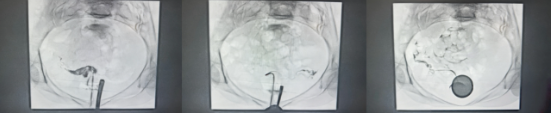

患者张女士(化名)因婚后多年未孕跨省前来就诊,造影显示双侧输卵管堵塞,进一步三维超声离奇发现:先天性生殖系统畸形——双宫颈、双宫腔(即两个独立宫颈+两个分离的子宫腔)

常规造影剂推注会瞬间弥散,无法在双宫腔结构中提供精细路径。谭一清教授果断采用微量造影分步显影法——每一针造影剂仅推注0.2毫升,逐层“绘制”宫腔三维形态,在屏幕上像拼图一样,一点点拼出两个宫腔的完整轮廓。

依据宫腔轮廓反向推断,输卵管开口极有可能隐藏在右侧宫角肌性隔断的后方。但这个位置,常规导管根本无法触及。谭一清教授立即换用头端可塑形微导管,将导管头端弯成15度的完美弧度,绕过错综复杂的肌性隔断,稳稳抵达目标位置——误差不超过1毫米。

导丝即将通过闭塞段时,阻力突然增大,屏幕显示导丝前方疑似存在坚韧的纤维化组织。强行通过,可能导致假道形成甚至穿孔。谭一清教授当机立断,采用娴熟的微幅震颤,配合少量局部润滑剂,让导丝像“水刀”一样,顺着组织间隙自然滑过。屏幕上,导丝尖端轻轻一跃,当造影剂如释重负般在输卵管弥散开来——通路打开了!